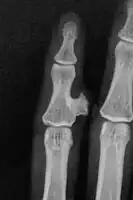

Medical imaging usually shows a well-defined wide-based bony growth on the surface of bone.[5] It can be pedunculated and irregular, giving it a "bizarre" appearance, and is not connected to underlying bone.[2]

X-ray hand, BPOP 2nd metacarpal -

X-ray hand, BPOP 2nd metacarpal (side view)